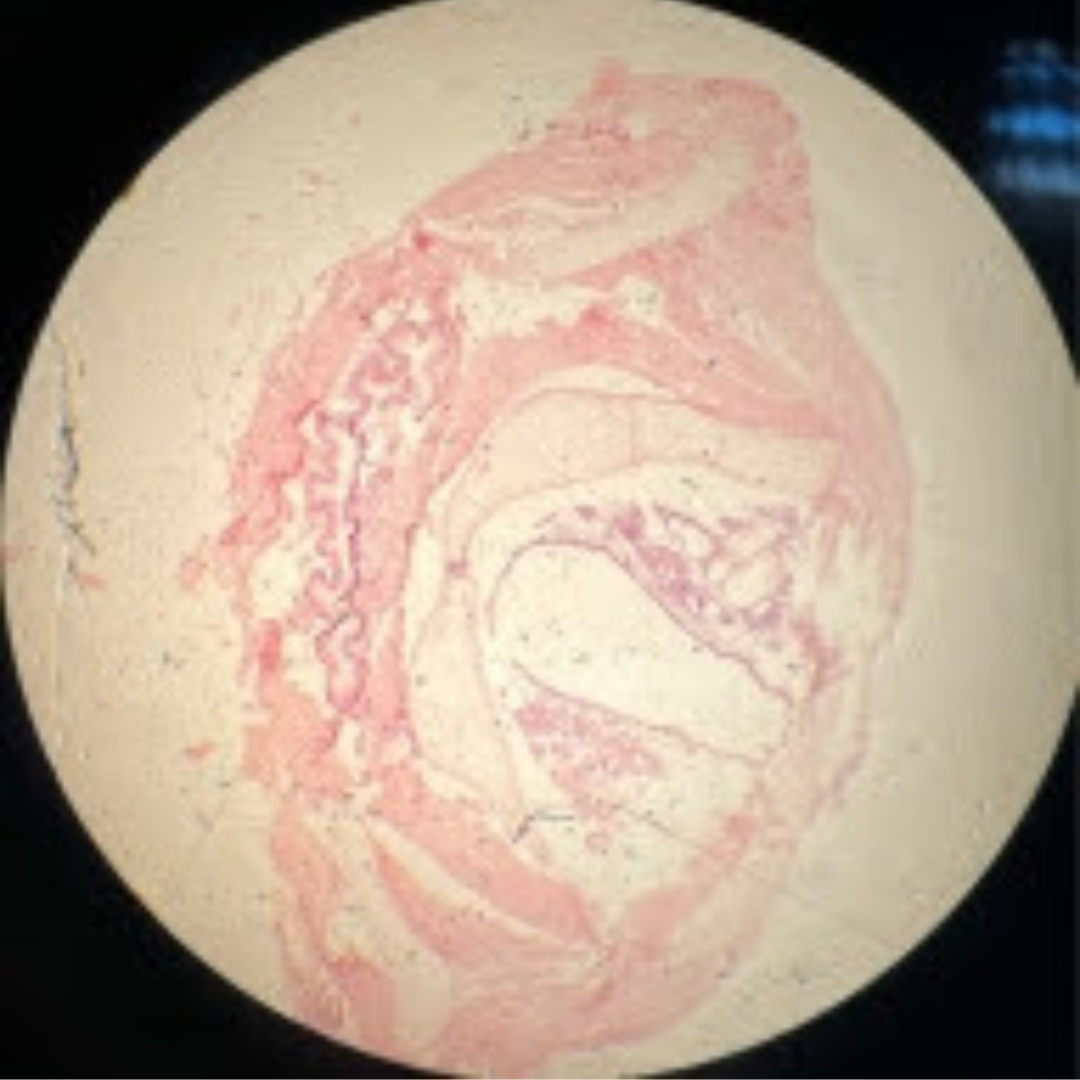

Lymphatic Vessel

Lymphatic Vessel

Lymphatic Vessel

Lymphatic Vessel

Lymphatic Vessel